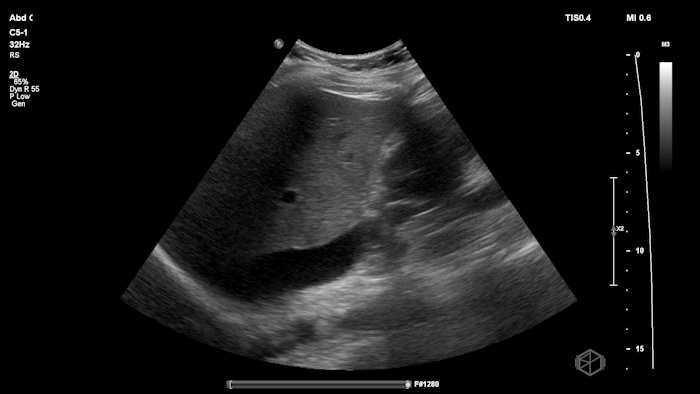

Dr.’s Konner and Maher scanned the patient and saw the following:

Initially it appears as though there is anechoic material above the liver and it does seem to make sharp angles. However, Dr. Konner and Dr. Maher utilized color doppler to evaluate the area and noted that it was simply the inferior vena cava. The patient ultimately had a CT scan that demonstrated no emergent findings.

Diagnosis: Potential false positive FAST - Inferior Vena Cava as a mimic of Free Fluid.

• Vessels can mimic free fluid. The IVC and other vascular structures sit right where we look for RUQ fluid and may appear anechoic in a single still frame. Use color doppler when not sure, free fluid will most commonly be at the caudal liver tip, and rarely just above the spine where the IVC sits.